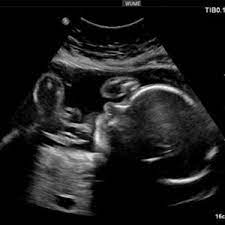

3d Ultraschall In Der 26 Ssw Baby Youtube

26 Ssw Die 26 Schwangerschaftswoche Gewicht Ultraschall Tipps Netmoms De